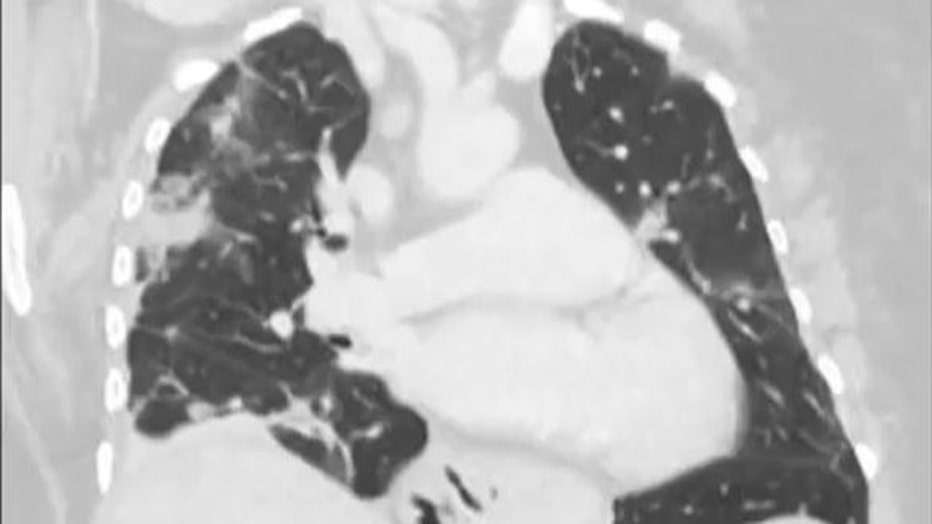

Doctors removed a worm "still alive and wiggling" from a woman's brain. (Credit: Australian National University via Storyful)

The woman had been admitted to the hospital after experiencing forgetfulness and worsening depression over three months. Scans showed changes in her brain.

A year earlier, she had been admitted to her local hospital in southeast New South Wales state with symptoms including abdominal pain, diarrhea, a dry cough and night sweats.

"This patient had been treated ... for what was a mystery illness that we thought ultimately was a immunological condition because we hadn’t been able to find a parasite before and then out of nowhere, this big lump appeared in the frontal part of her brain," Senanayake said.